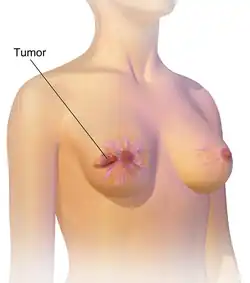

| An illustration of breast cancer | |

Breast cancer is a cancer that develops from breast tissue.[7] Signs of breast cancer may include a lump in the breast, a change in breast shape, dimpling of the skin, milk rejection, fluid coming from the nipple, a newly inverted nipple, or a red or scaly patch of skin.[1] In those with distant spread of the disease, there may be bone pain, swollen lymph nodes, shortness of breath, or yellow skin.[8]

Most people with breast cancer have no symptoms at the time of diagnosis; their tumor is detected by a breast cancer screening test.[22] For those who do have symptoms, a new lump in the breast is most common. Most breast lumps are not cancer, though lumps that are painless, hard, and with irregular edges are more likely to be cancerous.[23] Other symptoms include swelling or pain in the breast; dimpling, thickening, redness, or dryness of the breast skin; and pain, or inversion of the nipple.[23] Some may experience unusual discharge from the breasts, or swelling of the lymph nodes under the arms or along the collar bone.[23]